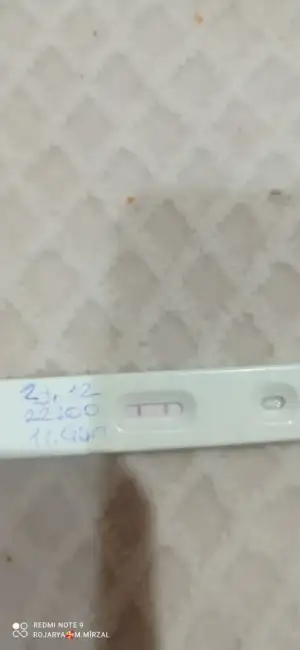

Cnm nasil yaptin anlatsan erkek bebek icin esin fala kan verdimi cin takvimi tuttumjZor oluyormuş evet bu ay takip yapıyorum sadece önümüzdeki ay nasipse hem doktor kontrolü hemde testle deneme yapacağım inşaallah